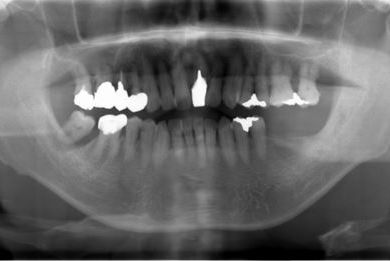

| 性別/年齢 | 男性 / 60歳 | ||||||||||||||||||||||||||||||||

| 主訴 | 右下奥歯の治療相談。(痛み・ぐらつき・物がかめない) | ||||||||||||||||||||||||||||||||

| 治療方針 | 左下奥の欠損部分をインプラント治療にて、機能的・審美的に回復を行う。 | ||||||||||||||||||||||||||||||||

| 治療内容 | インプラント2本、メタルボンドセラミッククラウン2本 | ||||||||||||||||||||||||||||||||

| 総治療費 | 680,610円 | ||||||||||||||||||||||||||||||||

| 治療期間 | 7ヶ月 |